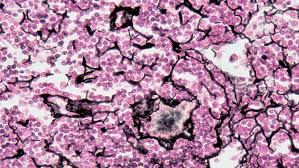

Once fascia is injured (stretched, pulled, torn, etc.), the microscopic fibers become disrupted and deranged. Instead of fibers running parallel to each other in an organized fashion with their normal degree of elasticity / flexibility, the fibers now run every possible direction — in all three dimensions. This is called a scar, and as you can see, scar tissue (no matter how microscopic it is) has an extremely diminished amount of organization and elasticity. Interlock the fingers from one hand with the fingers from the other, only do it with the fingers pointed in all directions. Now try to slide the hands back and forth. See the difference in flexibility? The fact that the fingers are running in a non-parallel fashion to each other greatly diminishes flexibility.